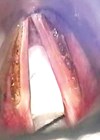

Gender-affirming voice surgery

Professor Ahmed Geneid is a laryngologist and phoniatrician at Helsinki University Hospital and a founding member of the International Association of TransVoice Surgeons. Here, he presents the intricacies and nuances of gender-affirming voice surgery after own hospital’s 30 years of...